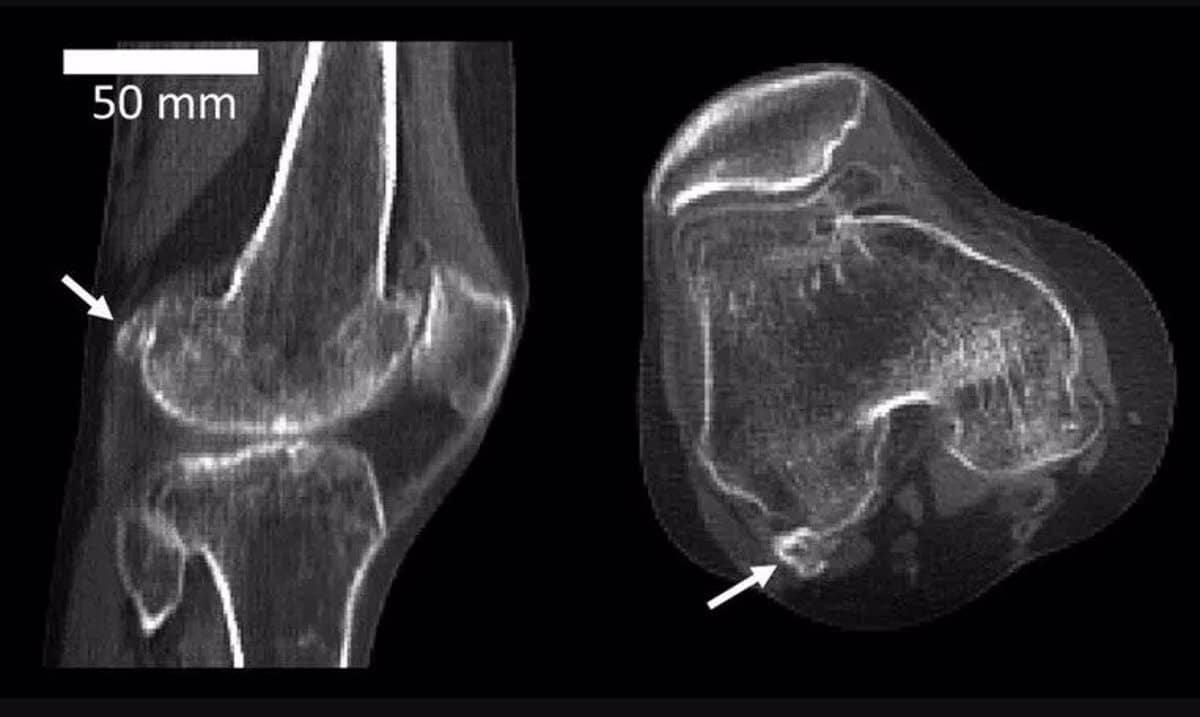

Боковая фабелла — сесамовидная кость, размером с небольшое кунжутное зернышко — на задней части колена человека / © Imperial College London

Способность ходить на двух ногах связали с эволюционными изменениями коленного сустава   Антропология

Авторы нового исследования показали, что важную роль в прямохождении человека могли сыграть эволюционные изменения в крошечной коленной сесамовидной кости — фабелле. Хотя такие кости есть у большинства приматов, они часто …